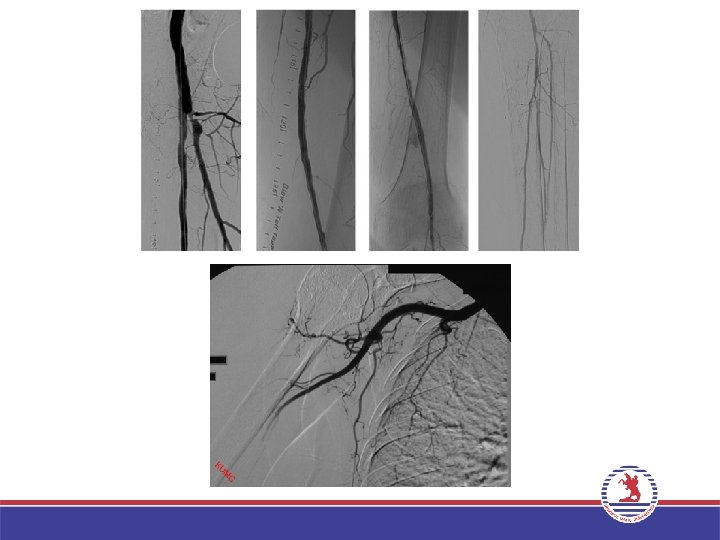

PERİFERİK ANJİYOGRAFİ • • Üst ve alt ekstremite arterleri Hepatik arter Splenik arter Mezenterik arterler Renal arter Bronşial arter Aortik dallar

PERİFERİK ANJİYOGRAFİ Yine Seldinger yöntemi kullanılarak periferik arteriyel yapıların (üst ektremite, alt ekstremite, renal, mezenterik vs. ) kontrast madde enjeksiyonu ile görüntülenmesidir. Temel anjiyografi tekniği (kateter yöntemi) ile yapılır. Endikasyonlar – – Damar darlıkları/tıkanıklıkları Travmatik damar yaralanmaları Arteriyovenöz fistül Vasküler malformasyonlar Arteriyovenöz malformasyon – Tümör kanlanması